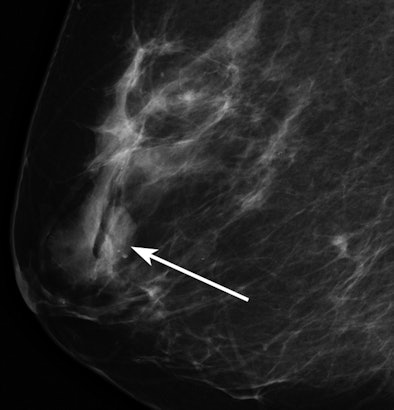

![]() |

| Mammographic image of a low-density mass (arrow). All images courtesy of the Radiological Society of North America. |